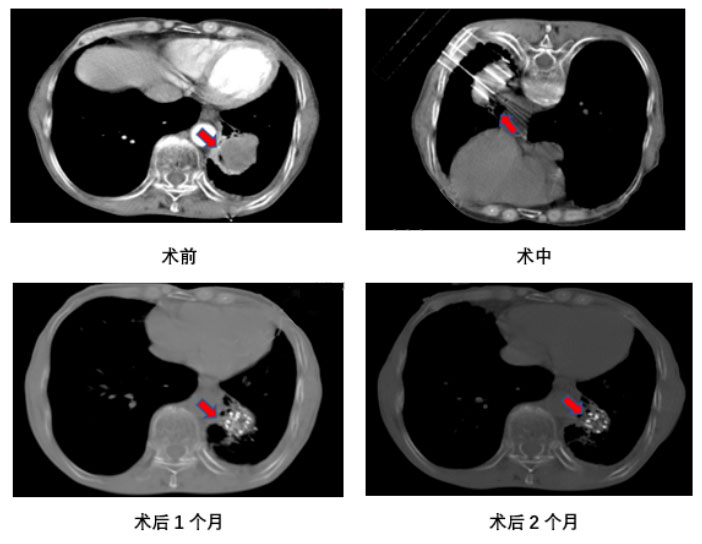

医生:首先要做术前增强CT做计划,确定需要放置的粒子数量、活度、以及穿刺路径和针数。然后手术中需要全身麻醉,医生通过CT引导将放射性粒子一颗一颗打入肿瘤内部。术后3天、1、2、3、6个月需要复查CT,确定肿瘤内粒子分布情况及肿瘤缩小情况。

病例1: 患者男,76岁,确诊小细胞肺癌2年,既往放疗及化疗史.

诊断为:左肺下叶中心型小细胞肺癌